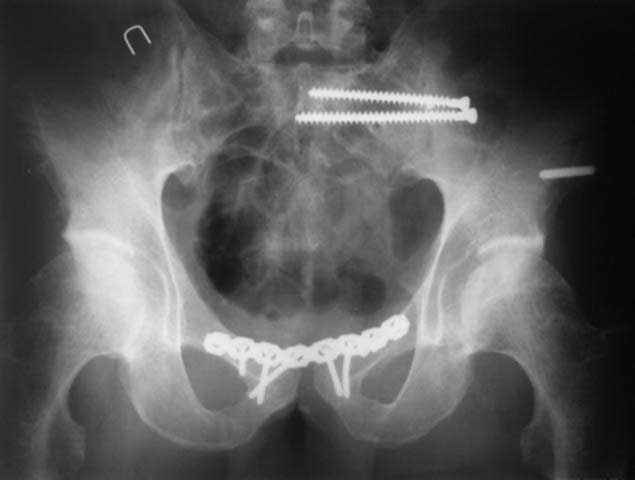

и 8месяцев после операции

> Результат через 10 дней и 8месяцев после операции

Да, забыл сказать - отличная работа, искренне восхищаюсь. Кость рубите по Judet (немного не разобрался по рисунку)?

Это наблюдение 5-летней давности тогда кровопотеря составила 2,5 литра. В настоящий момент мы теряем не более 0,7-1,5 литров при одностороннем повреждении и около 2,5-3 литров тогда, когда речь идет о двусторонних повреждениях. Клинический пример.